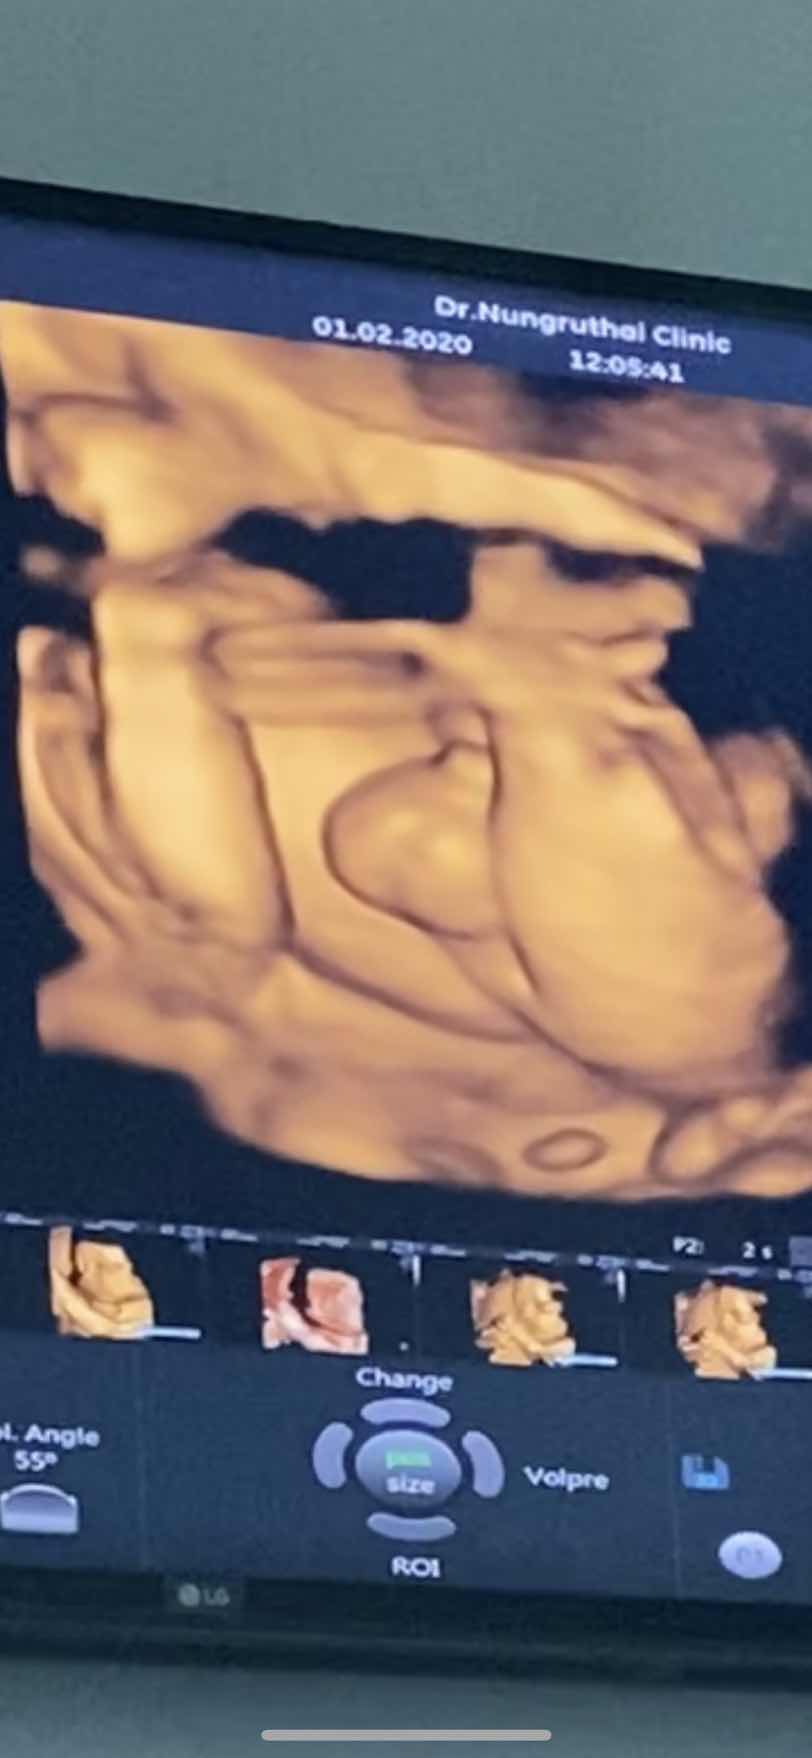

ลูกชายจร้า555

ชัดมากแม่555😂😂

5555ชัดเจนมากเลยค่ะ😂🥰

ว้ายลูก ชัดเจน

55555ยกขาโชว์กลีบชัดเจนเลยค่ะแม่ 😅

เป็นกลีบชัดเจนมากค่ะแม่ 😀

กลีบชัดเจนเลยค่ะแม่ ไม่ยอมเอาขาลงเลย😁